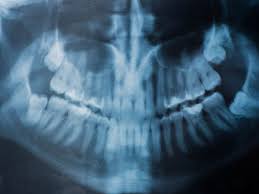

Panoramic Dental X Ray Showing A Crowding With A 10 Years Old Child Characterized By The Overlapping Of The Inciso Wisdom Teeth Wisdom Tooth Extraction Dental